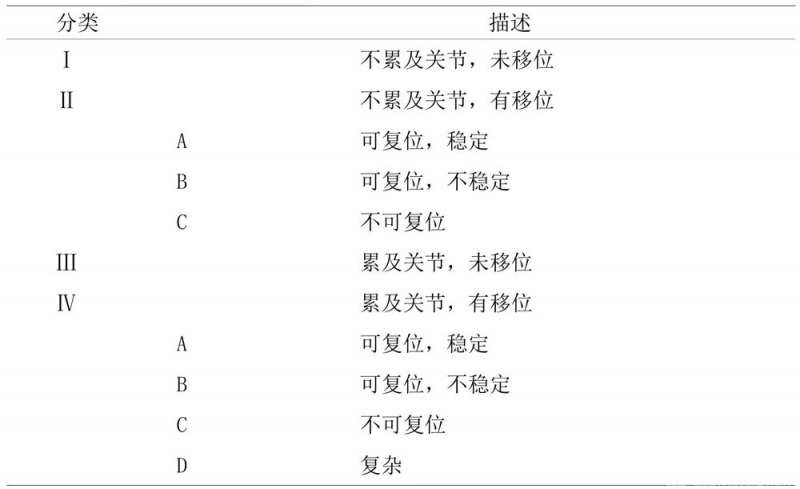

桡骨远端骨折通用的分类法在1990年被提出来。这个系统可以区分关节外的和关节内的骨折,以及稳定和不稳定的骨折,这种分类法是在治疗方案的基础上总结出来的(表1)。

表1 国际通用桡骨远端骨折分类